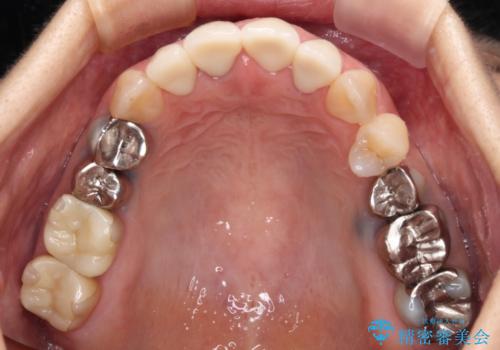

インプラントあるいはブリッジによる補綴治療が考えられましたが、前後の歯が大きな銀歯であったため、オールセラミックブリッジにより3本の歯を審美的に仕上げることとしました。

奥歯の治療をしている間に前歯の治療をどのように勧めるのか検討していただき、最終的には4歯を一度に治療し、審美的に仕上げることとしました。

ブリッジの支台歯は2本とも神経を取り除いている歯であるため、咬合力の強い方ですと、支台歯も歯根破折をするリスクがあります。

今回はそれほど咬合力が強いとは思われなかったため、ブリッジによる補綴治療を行いましたが、念のため、就寝時にはナイトガードとしてマウスピースを装着するようお願いしました。